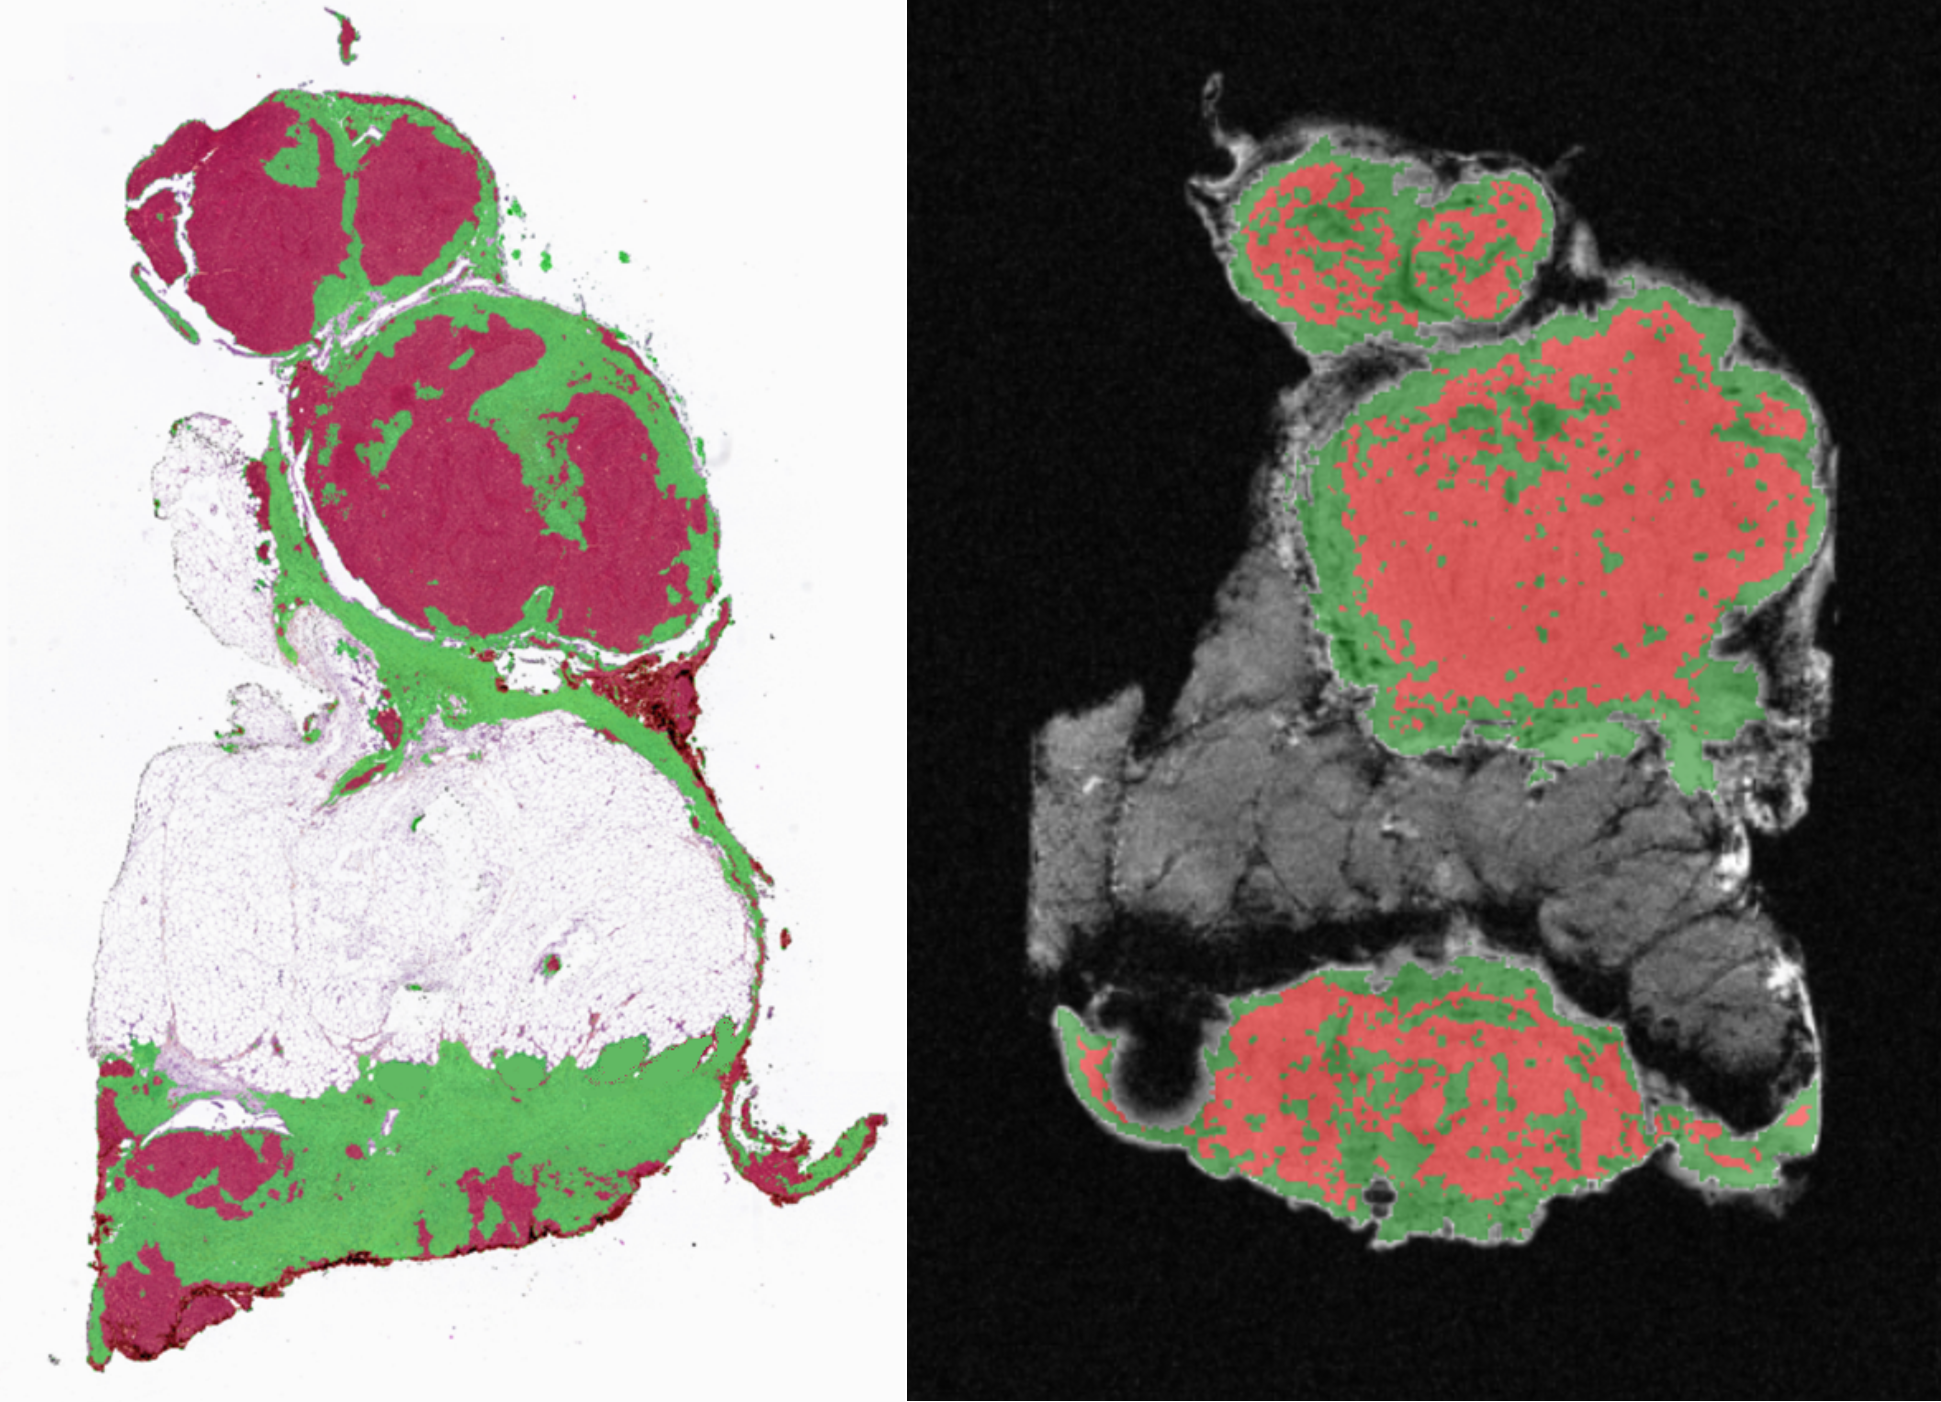

Pathomics, the large-scale quantitative analysis of whole-slide histology images, represents the first layer of clinically mineable information. From a single H&E slide, pipelines can segment tumor and stromal compartments, quantify immune cell infiltration, and extract rich morphological features.

Pathomics Example

We use QuPath for segmentation, and algorithms such as StarDist and Cellpose for detailed cellular feature extraction. New foundation models—UNI, CONCH, Virchow, Prov-GigaPath—enable powerful learned representations for classification, biomarker prediction, and survival modelling.

In HGSOC, this approach is key to capturing hallmarks of HRD and WGD, major determinants of genomic instability. These defects promote micronuclei formation and activate the cGAS–STING pathway, driving innate inflammation. Image-based signatures reflecting nuclear atypia, micronuclei burden, mitotic abnormalities, and immune/stromal changes offer a scalable readout of these processes.